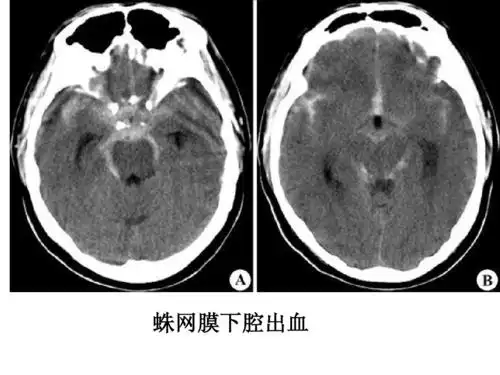

影像总结头颅ct基本知识与常见病变